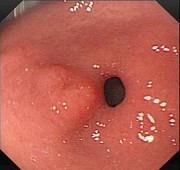

问题 患者,男,59岁,上腹不适2周,查体:心肺腹未见异常。电子胃镜图片及超声内镜如下,进一步要做的最佳治疗方案为 ( )

选项 A.电子胃镜下切除 B.外科手术切除 C.电子胃镜联合腹腔镜切除 D.随访观察 E.口服抗肿瘤药

答案 C